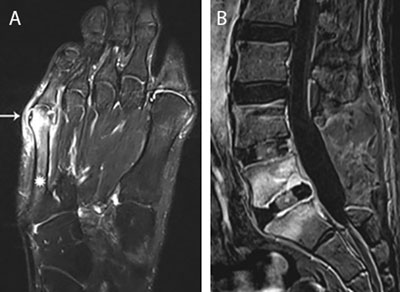

Figure 1

Main routes of infectious spread. (a) Infectious spread from contiguous infected tailors bunion. Axial T1-weighted image (WI) with Fat Suppression (Fat–Sat) after gadolinium contrast administration shows an inflamed bunion (white arrow) with adjacent enhancement of the distal aspect of the 5th metatarsal (asterisks). (b) Postoperative infectious spread. Postoperative spinal infection. Sagittal T1–WI with Fat–Sat after gadolinium contrast administration. Note laminectomy L4 and L5 with placement of intervertebral cages. Extensive enhancement of L5 and S1 with rim enhancement of the intervertebral cage L5–S1 in keeping with postoperative spondylodiscitis.